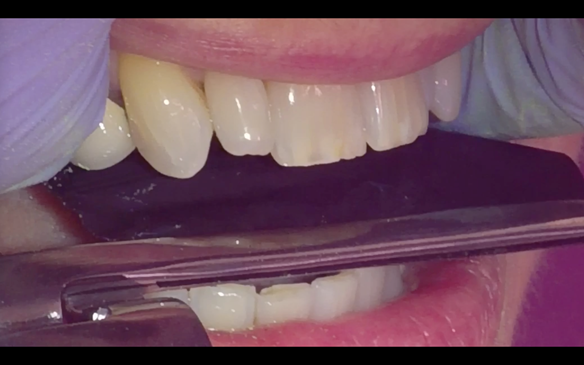

- Yellowing teeth

- Partial denture with new crowns (this is what the patient wanted - owing to the increased risk of implant failure due to type 1 diabetes)

The clinical situation and treatment process is shown in detail below with photographs. I (Finlay Sutton) provided the clinical work and Rowan Garstang provided the technical work.